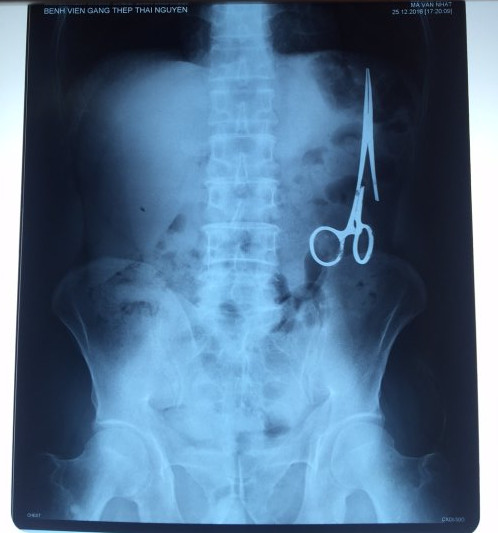

遺留在病人腹中的剪刀

據(jù)越南青年報(bào)1月2日報(bào)道,在越南首都河內(nèi)醫(yī)療專家的幫助下,越南東北部的太原?。═hai Nguyen)鑄鋼醫(yī)院的醫(yī)生日前從54歲患者M(jìn).V.N腹中取出一把醫(yī)用剪刀。這把剪刀是此前曾為M.V.N手術(shù)的醫(yī)生遺留的,已經(jīng)在其腹中待了18年時間。

醫(yī)務(wù)人員表示,這把剪刀遺留在病人腹部左側(cè),與結(jié)腸緊挨著。剪刀的把手已經(jīng)生銹,部分器官也已經(jīng)與剪刀粘連起來。但在過去多年中,M.V.N沒有任何不適感覺,也從未因?yàn)榱粼诟怪械募舻兑l(fā)的相關(guān)問題去看過醫(yī)生。直到2016年12月,M.V.N因?yàn)樵庥隽艘粓鲕嚨?,才到鑄鋼醫(yī)院進(jìn)行身體檢查。

超聲波檢查顯示,M.V.N的腸子中有個奇怪物體,看起來就像醫(yī)用剪刀。M.V.N證實(shí),他曾于1998年6月份在北江省綜合醫(yī)院接受手術(shù),在此后也從未進(jìn)行過任何手術(shù)。近來,他感到腹部有些疼痛,并試圖通過服用藥物治療。12月27日,M.V.N回到北江省綜合醫(yī)院再次進(jìn)行超聲波檢查,顯示其腹部的確存在怪異物體。